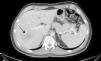

La evolución del paciente mejora, lo que permite practicar TC toraco-abdominal que revela afectación pulmonar bilateral con edema intersticial compatible con el diagnóstico de neumonía por PJ y advierte extensos cambios inflamatorios en parénquima hepático (fig. 2). Con la orientación de colangitis y focos de abcesificación, se procede a punción-aspiración con aguja fina eco-guiada que obtiene líquido purulento en el que crece Propinebacterium acnes (no se descarta contaminación).